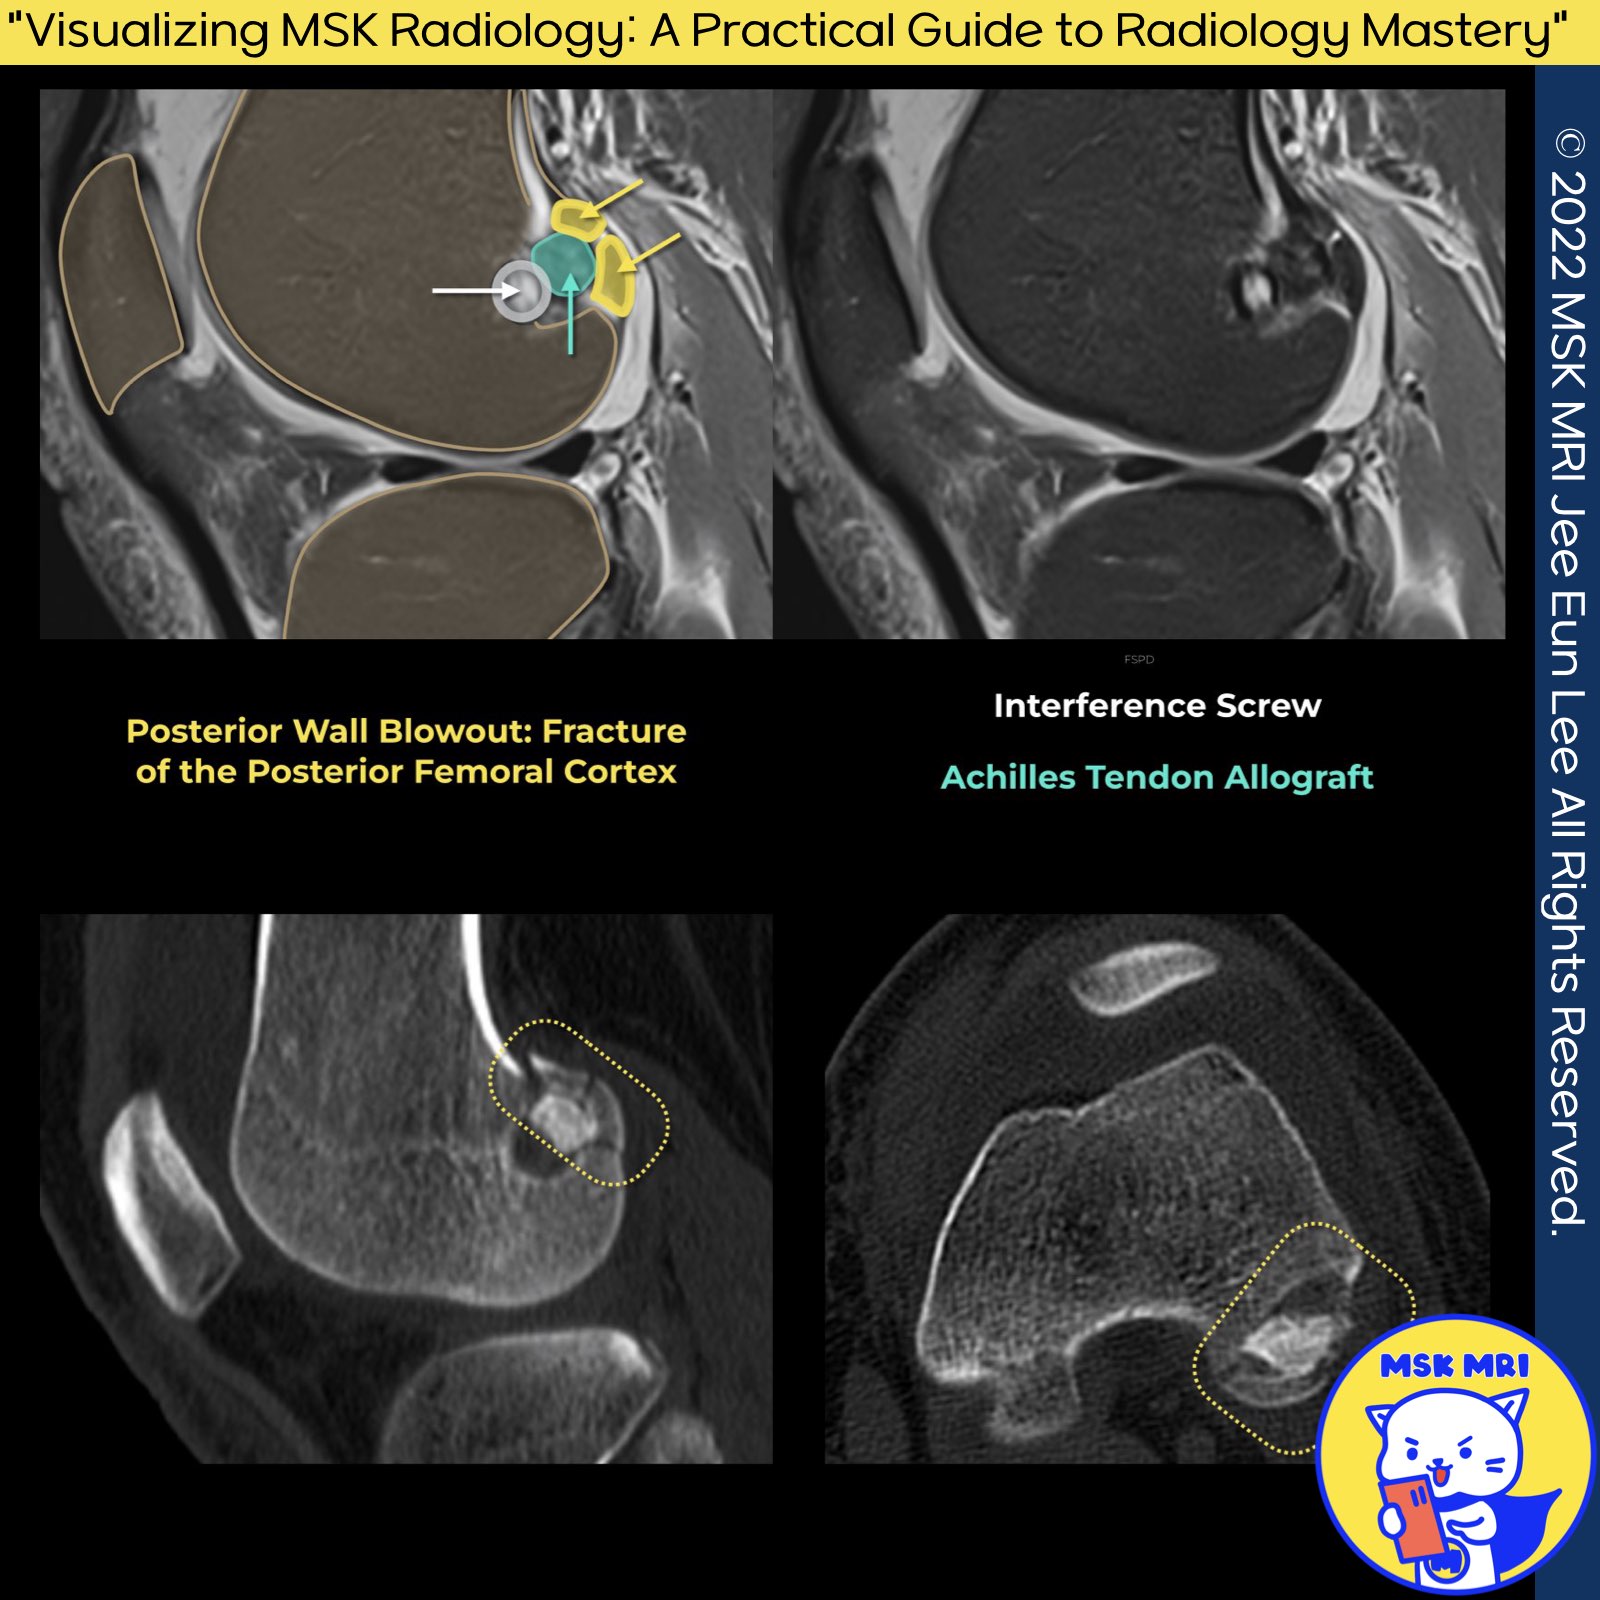

📌 Femoral Tunnel Posterior Wall Fracture

1️⃣ Impact of Tunnel Malposition

- Anterior malposition: Rotational laxity or graft impingement

- Posterior placement: Breach of posterior femoral cortex, lack of fixation

2️⃣ Consequences of Posterior Wall Violation

- Known as posterior wall blowout, Occurs distally at the tunnel's aperture Near the medial aspect of the lateral femoral condyle

- Devastating intraoperative complication in ACL reconstruction

- Leads to loss of graft fixation or early graft failure

Orthop J Sports Med. 2016 Jun 9;4(6):2325967116652122